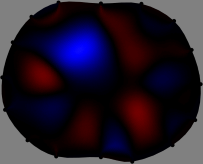

Figs. 3 and 4 compare the performance of the proposed FER method in (20) with the standard regularized least-squares method ((19) when \mathcal{R} is the identity matrix). The regularization parameter of the standard method was heuristically chosen for its best performance, and the parameter of the FER method was set to be one of three different values λ=0.05,0.2,𝜆0.050.2\lambda=0.05,0.2,\infty. The injection current was 1 mARMSRMS{}_{\tiny{\mbox{RMS}}} at 100 kHz, and the frame rate was 9 frames per second. The reference frame at t0subscript𝑡0t_{0} was obtained from the maximum expiration state. The measured data, 𝐕˙(tm)˙𝐕subscript𝑡𝑚\dot{\mathbf{V}}(t_{m}), represent the voltage differences between each time tmsubscript𝑡𝑚t_{m} and t0subscript𝑡0t_{0}. The blue regions, which denote where conductivity decreased by inhaled air, increased during inspiration and decreased during expiration. The FER method with λ=𝜆\lambda=\infty was clearly more robust than the standard method that produced more artifacts originated from the inversion process.

Figure 3: The reconstructed images of the conductivity change of the subject A by the standard regularized least square method and the proposed fidelity-embedded regularization (FER) method for three difference values λ=0.05,0.2,𝜆0.050.2\lambda=0.05,0.2,\infty. Here, the time step is 0.22 seconds (tm+2tm0.22subscript𝑡𝑚2subscript𝑡𝑚0.22t_{m+2}-t_{m}\approx 0.22).